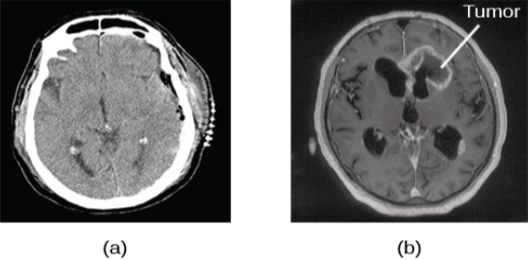

Image (a) shows a brain scan where the brain matter’s appearance is fairly uniform. Image (b) shows a section of the brain that looks different from the surrounding tissue and is labeled “tumor.”

Figure 3.29 A CT scan can be used to show brain tumors. (a) The image on the left shows a healthy brain, whereas (b) the image on the right indicates a brain tumor in the left frontal lobe. (credit a: modification of work by “Aceofhearts1968″/Wikimedia Commons; credit b: modification of work by Roland Schmitt et al)